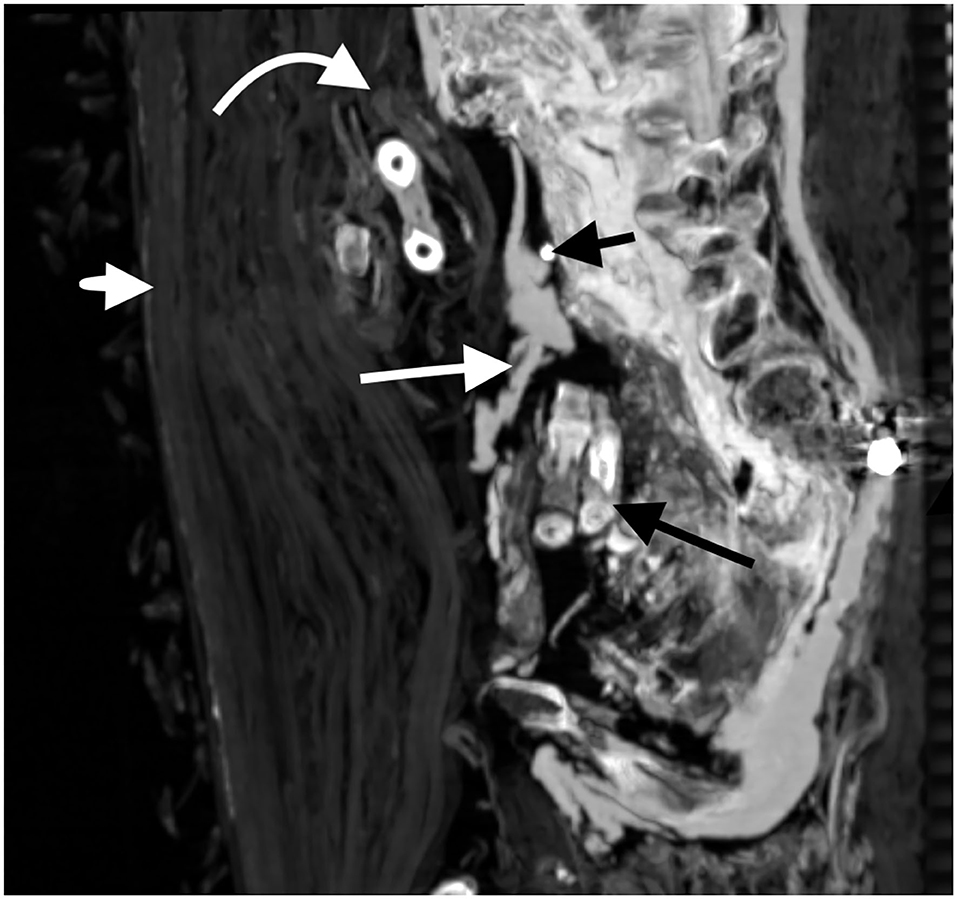

También se encontraron treinta amuletos/piezas de joyería. Amuletos de metal, cuarzo, piedra y arcilla cocida de varias formas y diseños fueron envueltos con la momia en diferentes lugares, con uno sobre el corazón y dos colocados dentro de la cavidad anormal. Los embalsamadores habrían pronunciado hechizos y envuelto estos como protección para el difunto. Otros artículos incluyen un cinturón de 34 cuentas de oro colocadas en la parte inferior de la espalda de la momia, alfileres de hueso o marfil y clavos metálicos que se usan para sujetar envolturas y extremidades en posición.

La evidencia de ladrones de tumbas también estaba presente. El brazo izquierdo fue desarticulado y luego vuelto a envolver extendido junto al cuerpo de la momia. El brazo derecho de la momia, sin embargo, está doblado por el codo con el antebrazo superpuesto al abdomen, lo que indica que probablemente ambos brazos alguna vez estuvieron cruzados de la misma manera. Dos dedos de la mano izquierda también fueron desmembrados, probablemente por ladrones de tumbas, y fueron localizados dentro de un gran defecto de la pared de la cavidad abdominal. Más notable aún, el cuello de la momia había sido cortado, la cabeza decapitada y se volvió a unir con una banda de lino tratada con resina con un amuleto colocado debajo.